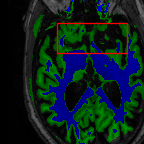

Sparsity LI 2D CNN 3D CNN Ours GT

4 Refer to caption (a) 0.6787/0.7972 Refer to caption (b) 0.8143/0.8776 Refer to caption (c) 0.8190/0.8714 Refer to caption (d) 0.8664/0.9085 Refer to caption (e) GM/WM

Refer to caption (f) 0.6808/0.7161 Refer to caption (g) 0.8103/0.8631 Refer to caption (h) 0.7950/0.8606 Refer to caption (i) 0.8598/0.9115 Refer to caption (j) GM/WM

Figure 6: Visual comparison of gray matter (Green)/white matter (Blue) segmentation over different methods, with respective DICE scores listed under the images.

In Fig. 6, we demonstrate the advantage of the proposed method in brain matter segmentation. It is clear that although 2D and 3D CNN generates visually plausible interpolation as presented in Fig. 5, the brain matters are easily misclassified due to incorrect anatomical structures and blurred details.